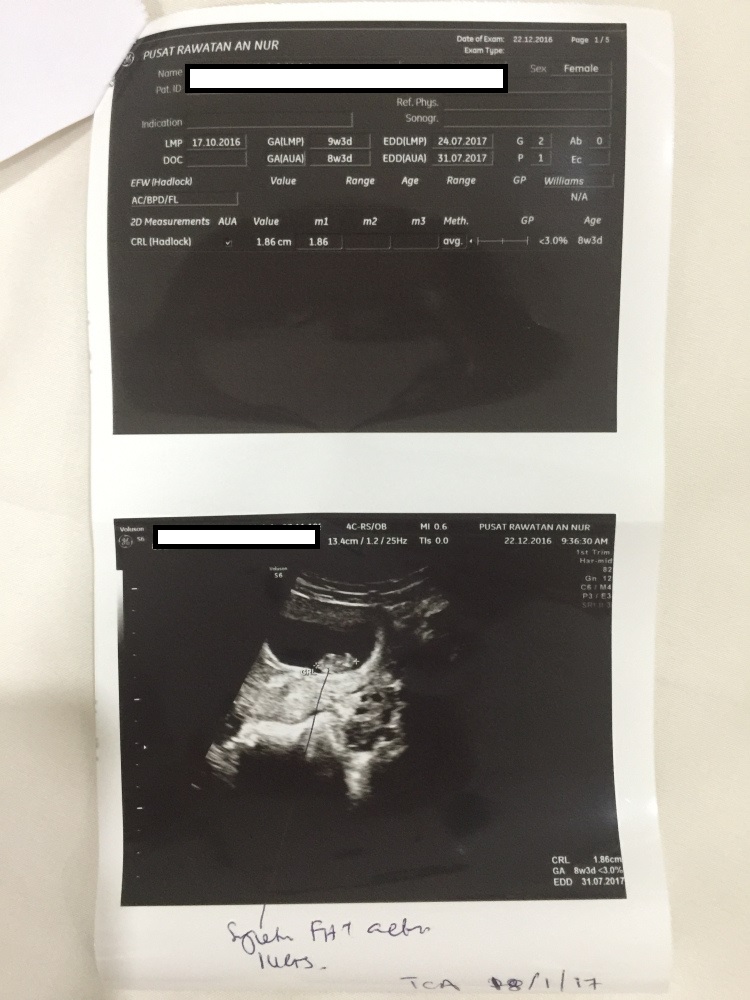

[Updated December 22, 2016 – 13.21 pm]

- Assalammualaikum, Alhamdulillah sudah memasuki minggu ke 8 sudah wife saya sedang pregnant anak saya yang kedua.

- Kemudian buat lagi scan di Pusat Rawatan An Nur pada 22 Dec 2016 (hari ini)

Minggu ke-8